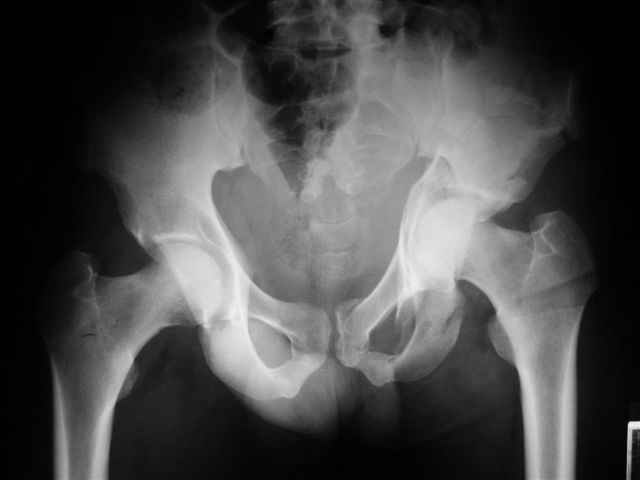

Уважаемые коллеги,43 летний мужчина, попав в автоаварию 13.10.2004, получил оскольчатый перелом обеих колонн левой вертлужной впадины.

На рентгенограммах - высокий двухколонный перелом вертлужной впадины с нарушением конгруэнтности, имеется обратная клиновидность суставной щели.

Учитывая молодой возраст пациента, желательна восстановительная операция.